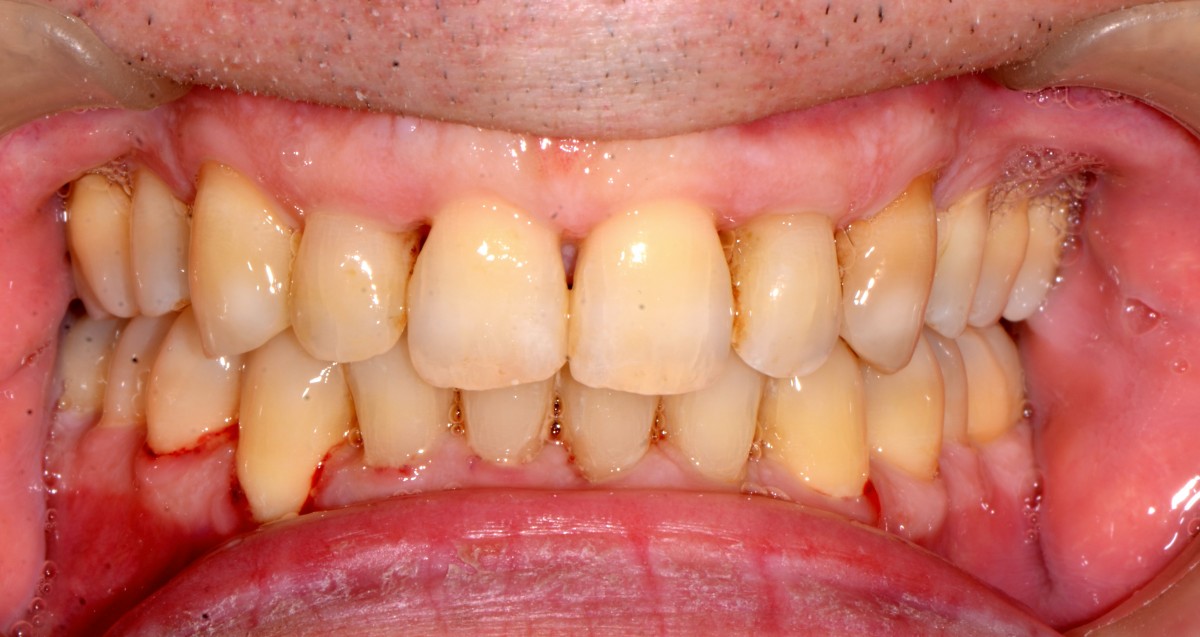

G.L., 51 years old patient, pre- sented to the clinic with Class I malocclusion, deep bite with complete coverage of lower in- cisors, big median diastema between teeth #11 and #21, lack of interdental papilla and poor oral hygiene (figs. 3, 4).

Lower incisors erupted verti- cally and created 2 planes of occlusion and exaggerated curve of spee in the lower arch. The upper lip “pushed” the an- terior incisors lingually and consequently the bite was deepened. Oral hygiene is poor mainly due to the crowding of the lower incisors. The upper diastema resulted in the loss of the interdental papilla between the central incisors (figs. 5, 6).

Patient had gone through pre- vious orthodontic treatment

with extraction of upper first premolars (#14, #24). Space between #11-#21 is slowly opened during the years and space start to develop distally to the upper lateral incisors. Lower incisors are hitting traumatically the palate creat- ing proliferation of the epithe- lium and constant inflamma- tion. Lower anterior crowding is around 4.5 mm (#33-#43) (figs. 7, 8).